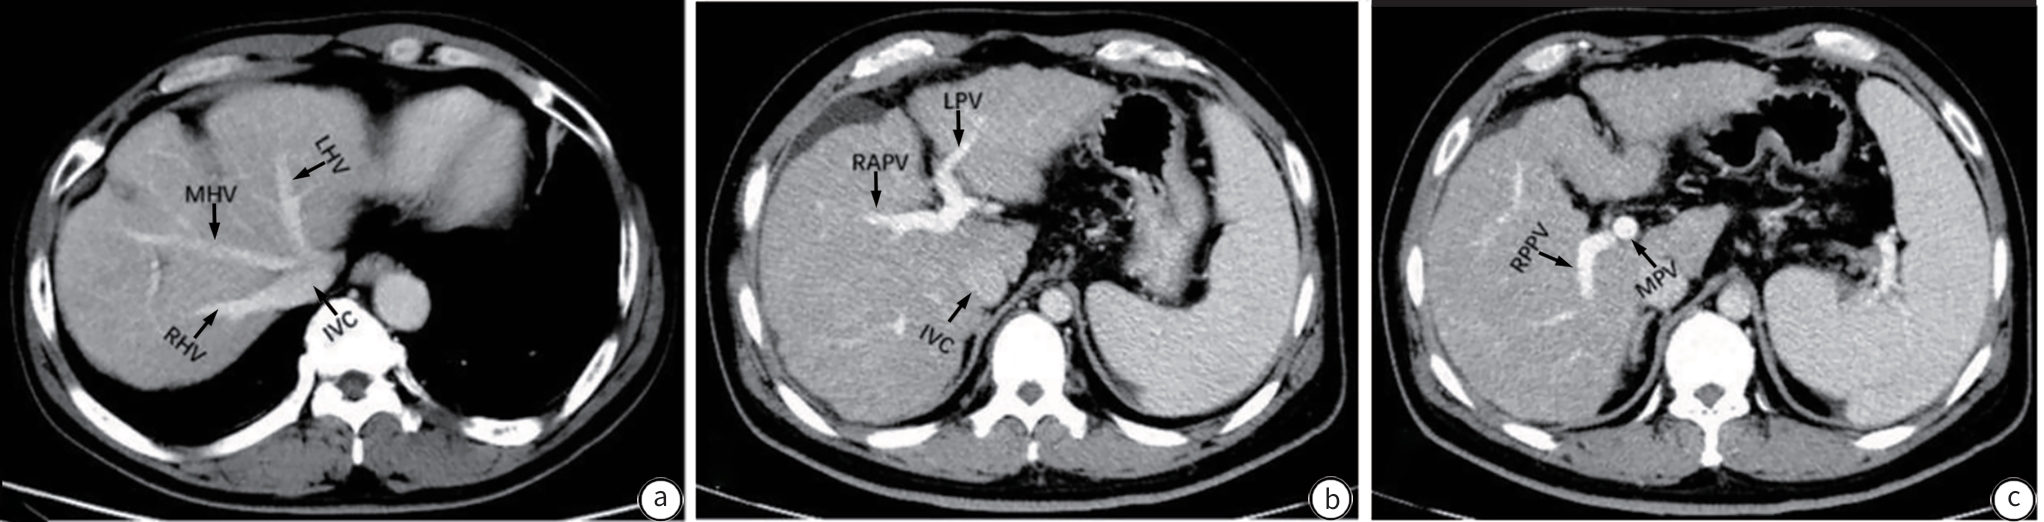

Three-dimensional CT reconstruction of the hepatic pedicle based on the Laennec’s capsule and the development and validation of extra-sheath dissection/occlusion clamp

Zhiyu LIN, Xin XIA, Huan LEI, Yuchuan LUO, Long CHENG, Hongyin LIANG, Tao WANG

2025, 41(10): 2118-2124. DOI: 10.12449/JCH251023

Abstract:

Objective  To investigate the anatomical features of three-dimensional (3D) reconstruction of the hepatic pedicle based on the Laennec’s capsule, as well as its application value in the development of extra-sheath dissection/occlusion clamp and precise hepatectomy.  Methods  A retrospective analysis was performed for the abdominal contrast-enhanced CT data of 100 patients without anatomical abnormalities of the hepatic pedicle in The General Hospital of Western Theater Command from January 2021 to June 2024. The Hisense CAS system combined with the 3D U-net deep learning algorithm was used for 3D reconstruction of the hepatic pedicle at the level of Laennec’s capsule, and the hepatic pedicle was measured in terms of the length, outer diameter, and angle of the main trunk and branches. An extra-sheath hepatic pedicle dissection/occlusion clamp was developed based on the above measurements, and a total of 30 patients scheduled for right hemihepatectomy were enrolled and randomly divided into device group and control group, with 15 patients in each group. The two groups were compared in terms of hepatic pedicle handling time, time of operation, intraoperative blood loss, and the incidence rate of bile duct injury. The independent-samples t test was used for comparison of continuous data between two groups, and the Fisher’s exact test was used for comparison of categorical data between two groups.  Results  The results of 3D reconstruction revealed four variants in the main trunk branches of the hepatic pedicle, with type Ⅰ (left-right branching) accounting for 88% (88/100), type Ⅱ (trifurcation type) accounting for 5% (5/100), type Ⅲ (right anterior branching) accounting for 5% (5/100), and type Ⅳ (special type) accounting for 2% (2/100). The outer diameter of the main hepatic pedicle was 24.10±6.16 mm, the length of the left main branch was 20.59±6.38 mm, and the length of the right main branch was 21.99±7.98 mm. Compared with the control group, the device group had significantly shorter hepatic pedicle handling time (14.10±1.30 minutes vs 17.50±2.00 minutes, t=-5.620, P=0.001) and time of operation (217.00±28.28 minutes vs 241.87±19.49 minutes, t=-2.804, P=0.009). The device group had a significantly lower incidence rate of bile duct injury than the control group (0 vs 20%, P=0.031).  Conclusion  3D reconstruction based on the Laennec’s capsule can accurately display the anatomical variations of the hepatic pedicle. The extra-sheath hepatic pedicle dissection/occlusion clamp developed based on such data can optimize the process of hepatic pedicle management and improve surgical safety, and therefore, it holds promise for clinical application.